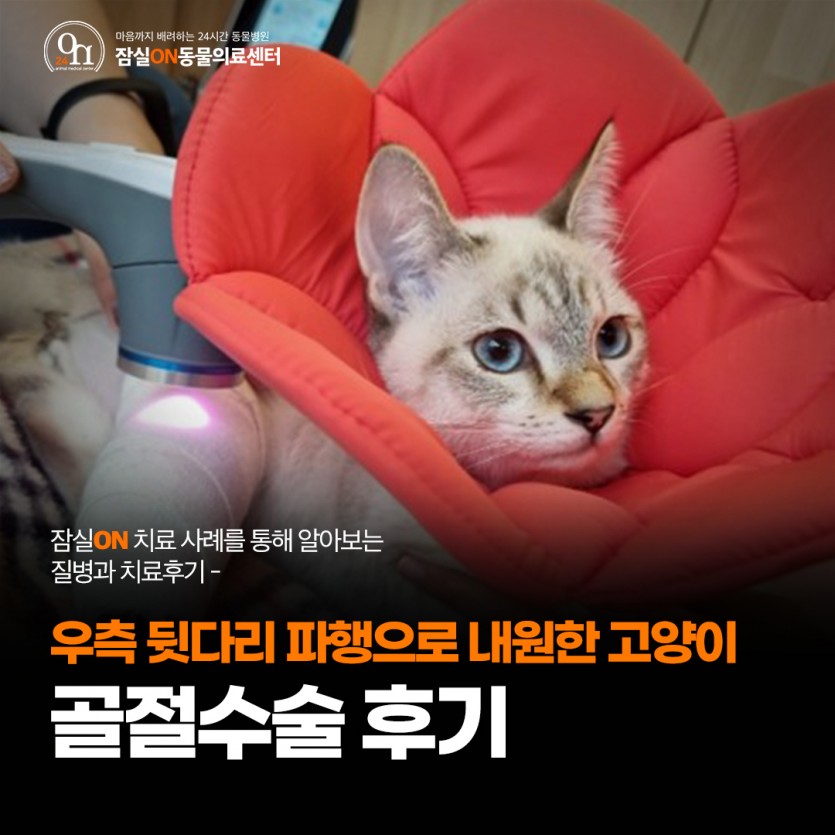

- 우측 뒷다리 파행으로 내원한 고양이의 골절수술 후기

고양이 뒷다리 골절수술 후기

5개월령의 먼치킨 고양이 아이가 우측 뒷다리 파행을 증상으로 내원했습니다.

저녁에 보호자님이 귀가를 해 보니 우측 후지를 딛지 못하고 있는 상황으로, 정확한 상황은 파악이 어렵지만 내원 당시 다리를 전혀 딛지 못하고 힘이 들어가지 않는 것을 미루어 보아 골절의 가능성이 있는 상황이었습니다. 고양이는 높은 곳을 오르고 뛰어내리는 습성을 가지고 있다보니 이러한 행동이 관절에 무리를 주거나 골절을 발생시킬 수 있습니다.

<수술 후 재활치료 중 - 좌: 레이저치료, 우: 산소챔버>